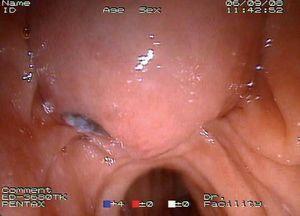

Mujer de 87 años que ingresa en el servicio de cirugía por ictericia, colangitis y pancreatitis aguda. Se instauró tratamiento con sueroterapia y antibióticos, que consiguió la estabilización hemodinámica de la paciente. En una colangiopancreatografía por resonancia magnética (fig. 1) se observó un defecto de repleción en el colédoco distal. Con la intención de desobstruir la vía biliar, se realizó una colangiopancreatografía retrógrada endoscópica (CPRE), empleando sedación consciente con midazolam y dolantina. En la endoscopia, la ampolla de Vater se encontró muy abultada, con un orificio en el que parecía entreverse una coledocolitiasis (fig. 2). Se realizó una esfinterotomía biliar amplia (fig. 3) y se extrajo una coledocolitiasis de 13 mm de diámetro máximo, que estaba impactada en la ampolla (fig. 4). La evolución de la paciente fue satisfactoria.